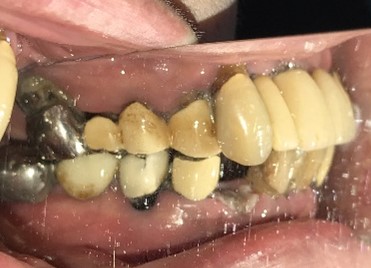

男性Iさん 50代(マグネット式入れ歯)

治療内容

歯周病が進行し深刻な状態でした。保存することができない歯が上4本、下3本ありましたので、抜歯し、残った歯上4本、下7本の歯周病治療を徹底的にし、それらの歯を活用し上下マグネット式総入れ歯を入れました。

After

【義歯を装着したところ】

【義歯を外したところ】

【マグネット式総入れ歯】

上顎

下顎